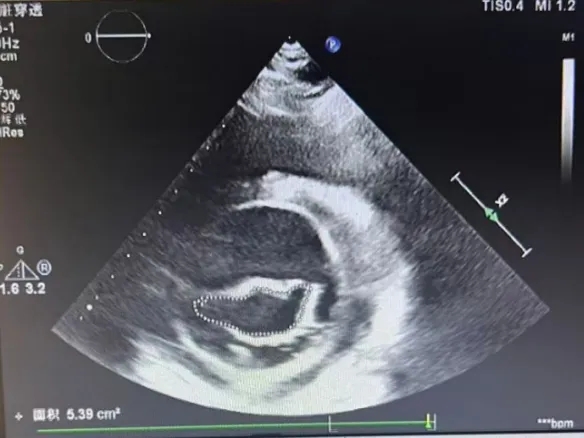

术前瓣口面积5.39cm²